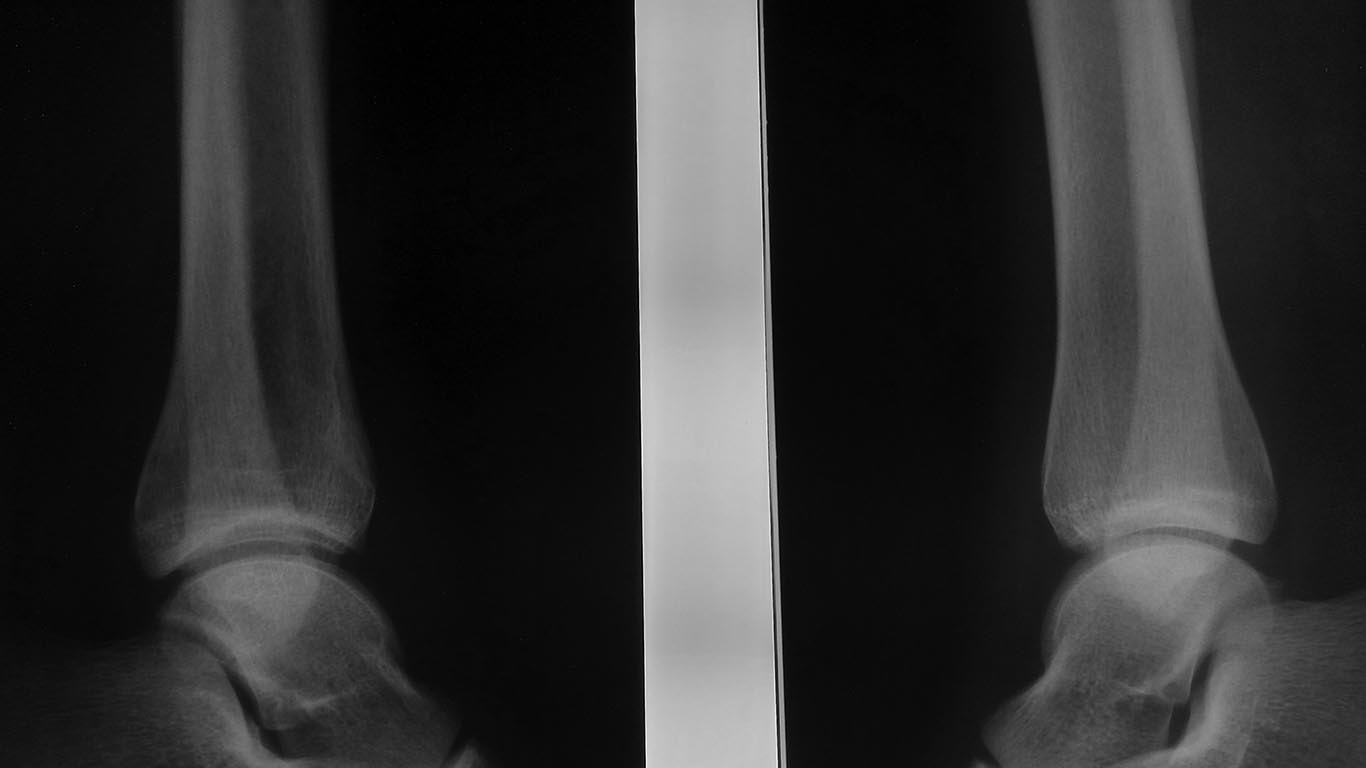

[Ortho] Последствия травмы у подростка

Снимки

Имя     : 2.jpg